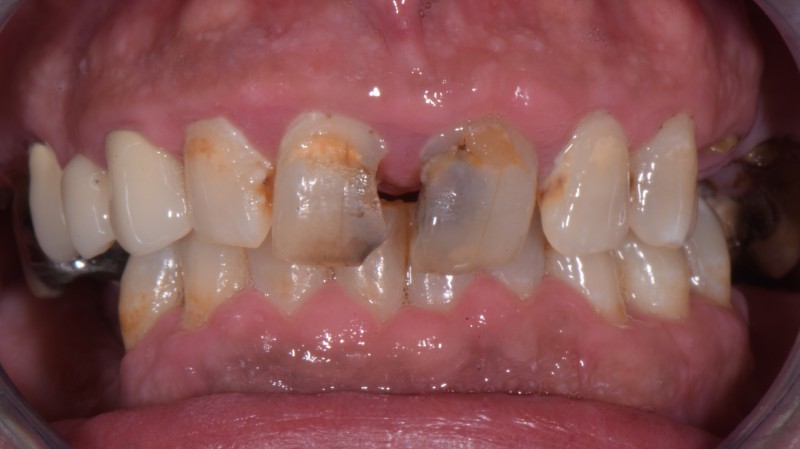

Paziente maschio 42 anni fobico numerosi denti assenti e altrettanti compromessi.

Il rapporto con il dentista non è stato facile in passato per questo motivo la situazione orale si è degradata nel tempo

Il Problema